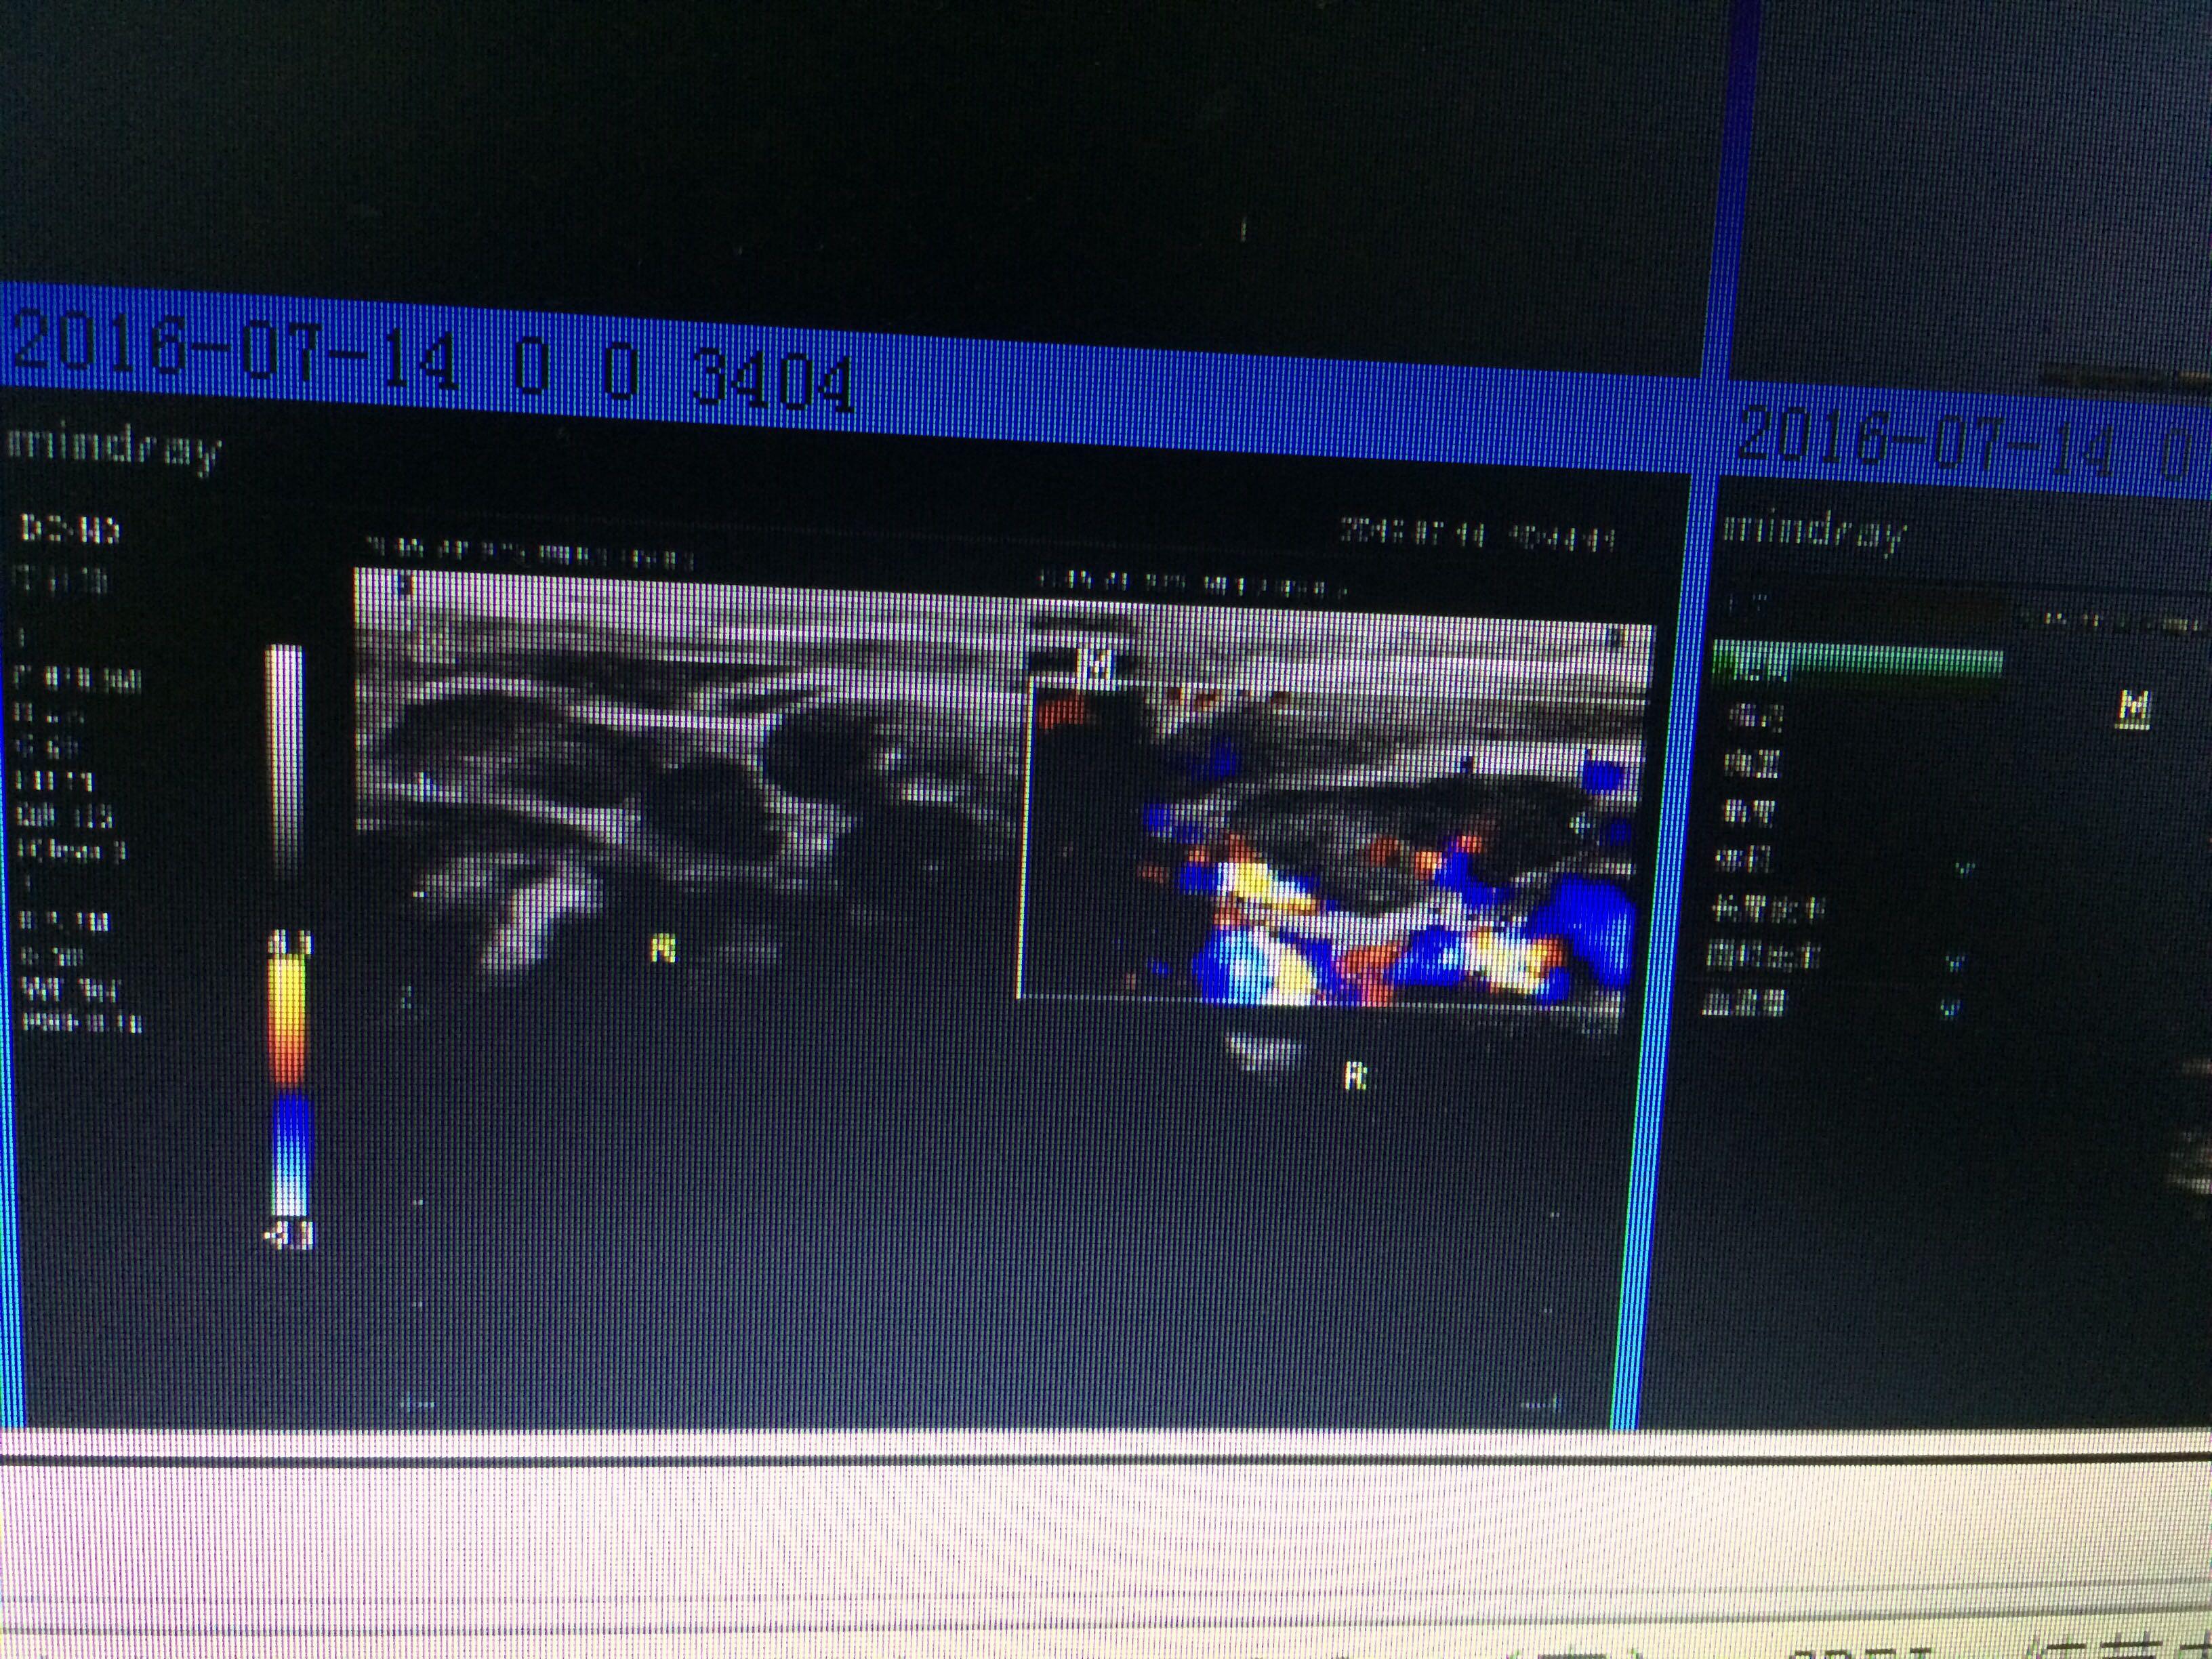

霍奇金经典型4个abvd疗程后彩超发现多出淋巴结肿大

图片尺寸2016x1512